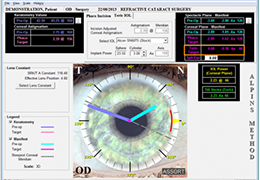

Designed for surgeons, Pro Surgical 3D makes it easy to view patient scans quickly. Pro Surgical 3D facilitates the optimal 3D treatment and assessment workflows based on X-ray CT and MRI scans – and best of all, it’s FREE!

Everyone – including surgeons, patients and their loved ones – benefits from being better informed by the wealth of information buried within CT and MRI scans. Pro Surgical 3D gives surgeons more information to develop optimal treatment plans for patients. It also helps patients and their support group better understand their medical condition and proposed treatment options.